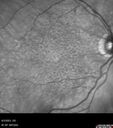

92 year old man The vision in the left eye has been declining for about 8 weeks. Prior to that the two eyes were similar. The left eye did have a prior retinal detachment. The RD was in the 1990's. It was repaired by Dr. Tom Ward. Dr. Cohen saw the patient afterward and did a lot of treatment for retinal tears. Medical Hx: BPH. Congestive Heart Failure. Hypertension, Systemic. Pure Hypercholesterolemia, Unspecified. Surgical Hx: Tonsillectomy. Appendectomy. Herniorrhaphy. Cataract Surgery. Systemic Meds: Avodart 0.5 mg. Calcium 500mg. Digitek 125mcg. Eliquis 5mg. Entresto 24mg. Lasix midodrine 5mg. Ocuvite. Propafenone 150mg. Vitamin D. Zocor 20mg. VA 20/25 OD, 20/200 OS IOP 8 OD, 12 OS

Wet AMD - Type 1 CNVM - RAP lesion77 views92 year old man with vision loss and very high PED. Because of worry about a PED tear, patient was treated with avastin, then lucentis, then eyelea, then vabysmo (progressively stronger meds)00000